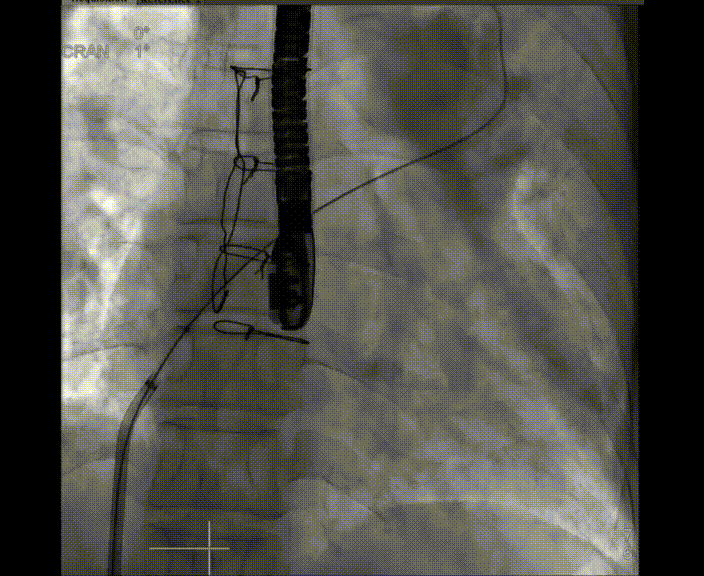

術中首先在局麻下穿刺股動脈、股靜脈,完成心導管檢查評估后轉為全麻,在食道超聲引導下穿刺房間隔,穿刺成功后將加硬導絲送入左上肺靜脈建立軌道,根據患者病情行球囊預擴張后植入6mm孔徑房間隔造孔支架,經透視及食道超聲評估支架左右盤展開良好,夾持于房間隔兩側,固定穩(wěn)定、位置良好,食道彩超顯示房水平右向左為主分流,分流孔直徑符合預期大小,心導管檢查評估達到預期效果,釋放造孔支架。術后12h患者下床活動,恢復順利,擬于近日完善術后評估后出院。